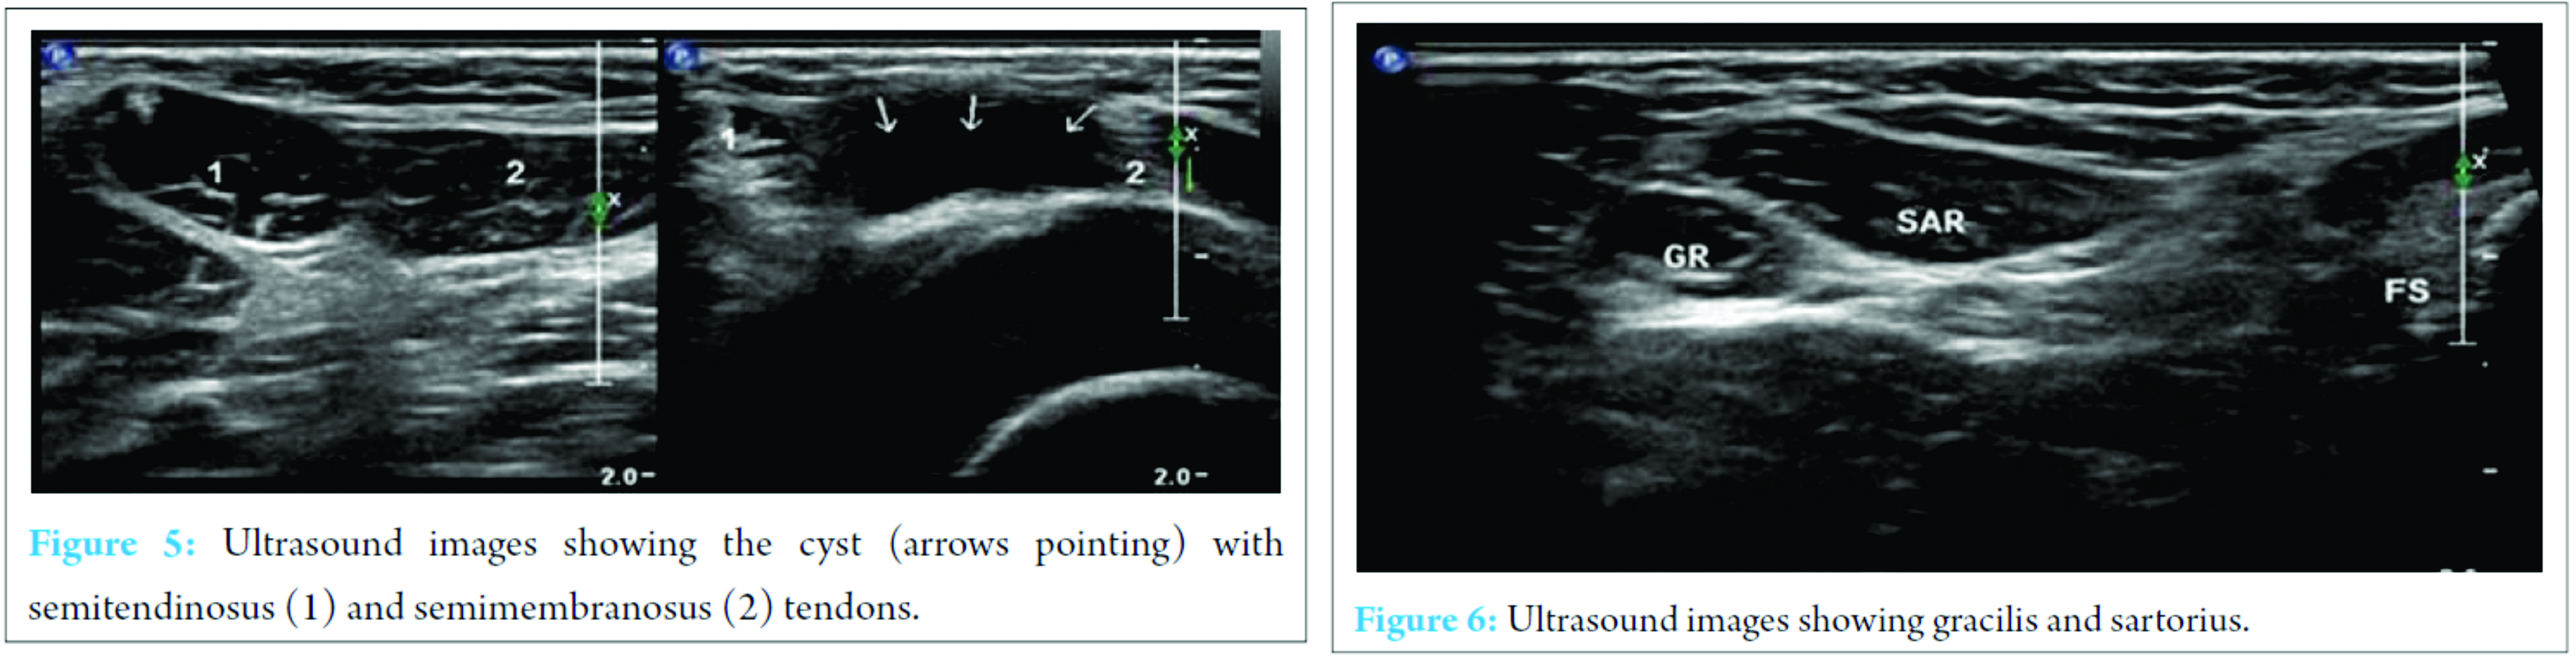

X-ray of the knee joint was unremarkable (Fig. 3, 4). Ultrasonography (USG) revealed a hypoechoic well-defined cystic lesion with clear contents is visualized on the antero-medial aspect of the left knee over the semitendinosus tendon. The lesion measures 25 mm × 10 mm. The lesion is causing splaying of the gracilis and sartorius muscles near knee; the lesion extends lower down and posteriorly and appears to fuse close to pes anserine insertion near the pulsation of the medial geniculate artery (Fig. 5, 6). Doppler USG showed no evidence of vascular involvement.

USG and magnetic resonance imaging (MRI) can differentiate a ganglion cyst from other soft tissue lesions and provide excellent information about the location and dimensions of the lesion along with its margins especially intratendinous cysts [1, 3, 16].

Intratendinous ganglion cyst is a relatively uncommon lesion. Incidence of the upper limb is more common than lower limbs. All cysts around the joints and tendons should undergo USG evaluation both preoperatively as well as postoperatively. We have presented the first case report of an intratendinous ganglion cyst of the semitendinosus tendon with findings using USG.